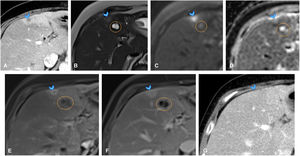

A 68-year-old woman with history of duodenal cancer (T2N0M0) treated surgically with cephalic duodenopancreatectomy, leaving her disease-free, attended the emergency department with fever and liver function abnormalities. (A) Axial slice of CT of the abdomen, identifying two new-onset hypodense liver lesions: one in segment VII (not shown) and another in segment IVa-b (arrowhead), with marked hypervascularisation in peripheral parenchyma. While these findings do not rule out metastases in the current clinical context, they could correspond to liver abscesses. (B) Axial slice from T2-weighted sequence of liver MRI showing the segment IVa-b lesion as mildly hyperintense, with even more hyperintense centre (arrowhead), adjacent to cyst (orange circle in B–F). Lesion appeared hypointense on T1 (not shown). (C, D) Axial slices from diffusion-weighted sequences of liver MRI showing no diffusion restriction in lesion (arrowheads). (E, F) Axial slices from dynamic liver MRI study, demonstrating ring-shaped arterial enhancement of lesion (E, arrowhead), which progressively increases in later phases (F, arrowhead). In the clinical context, and given absence of diffusion restriction, an abscess was considered the primary diagnosis, and antibiotic treatment was initiated. (G) Axial slice from early follow-up CT of the abdomen one month later, showing resolution of the lesions (arrowhead), confirming diagnosis of abscesses.